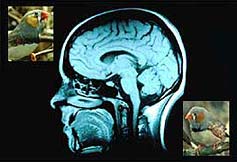

A leafy suburb in upstate New York is the unlikely setting for pioneering research into the human brain. But at his field research centre, scientist Fernando Nottebohm is using song birds like the canary, to unlock the secrets of how we remember and why we forget.

It used to be thought that babies are born with all the brain cells they would ever need - more than a hundred billion of them - and that as one ages, these cells start dying off irreversibly until death. But in the early 1980s, one scientist discovered that canaries grew new brain cells in order to learn the new mating songs they need each spring. Fernando Nottebohm wondered how they managed to do this and to his and the world's amazement discovered that the bird's brain grew and then shrank according to its behaviour. Eventually, other animals were found to have the ability to increase the size of their brains at will - rats, monkeys and finally, in the late 1990s, even the human adult brain showed small signs of new cell creation or “neurogenesis”.

Surrounded by more than 5000 canaries and 1500 Zebra Finches, Nottebohm and his team are teaching birds to sing new songs and analysing how their brains are acquiring this new information. As Rami Tzbar reports, they hope to discover whether this process can be 'turned on' in humans and used to slow down and maybe even reverse the progression of chronic and incurable conditions like Alzheimer's and Parkinson's disease.